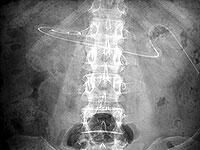

写真1は 70 歳、男性、糖尿病で慢性心不全の患者ですが、直腸に便塊がありカテーテルが持ち上げられ排液されませんでしたが、浣腸して注排液がスムースになりました。

55 歳、男性、糖尿病の患者で1月 26 日に導入後の写真です。

2004 年5月9日、カテーテル先端は左腸骨

2004 年5月 25 日、カテーテル先端は臍部

2004 年6月 17 日、カテーテル先端は左腸骨

2004 年7月8日、カテーテル先端は右上腹部

2004 年8月3日、カテーテル先端は左腸骨